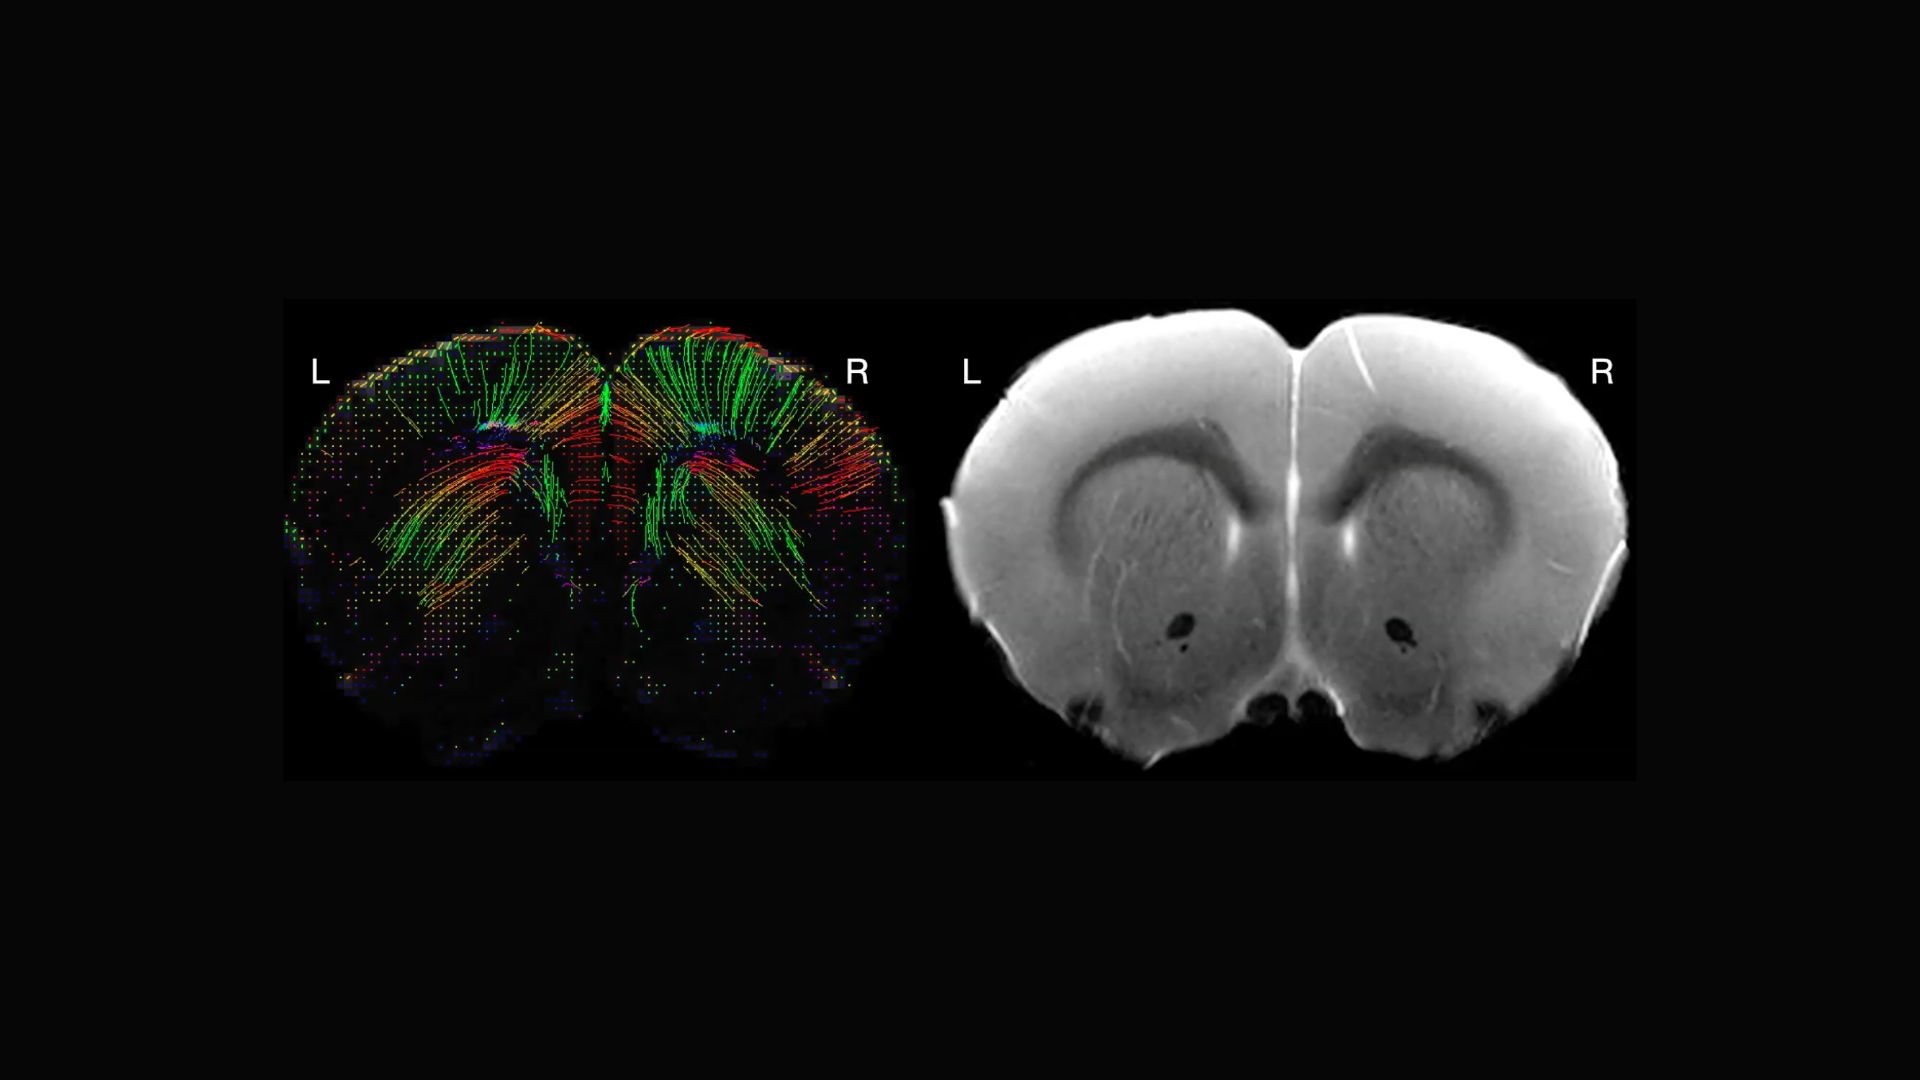

Exploring MRI's role in neuroscience research on model organisms Wu Neuroscience Model Organisms the genetic model organisms discussed in depth in the text—mus musculus (house. — in this review we will highlight the past and present techniques which have made, and continue to make, zebrafish an attractive model. — the model organism screening center (mosc) of the udn is a unique resource dedicated to utilizing informatics. — model organisms,. Neuroscience Model Organisms.

Exploring MRI's role in neuroscience research on model organisms Wu Neuroscience Model Organisms — by providing critical insights into these processes, decades of research using model organisms has been central. — model organisms, both common and unconventional, have been instrumental in uncovering basic principles of neural function. mit neuroscientists use a host of model organisms to study synaptic, neuronal and brain function, as well as to model. the genetic. Neuroscience Model Organisms.

Exploring MRI's role in neuroscience research on model organisms Wu Neuroscience Model Organisms — by providing critical insights into these processes, decades of research using model organisms has been central. the genetic model organisms discussed in depth in the text—mus musculus (house. — this issue combines insights from traditional models such as drosophila melanogaster and apis mellifera and. — the model organism screening center (mosc) of the udn is. Neuroscience Model Organisms.

Exploring MRI's role in neuroscience research on model organisms Wu Neuroscience Model Organisms — model organisms, both common and unconventional, have been instrumental in uncovering basic principles of neural function. — by providing critical insights into these processes, decades of research using model organisms has been central. The increasing diversity of model species currently employed in neuroscience broadens the scope of topics that can be conveniently and effectively explored. the. Neuroscience Model Organisms.